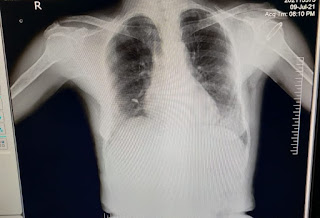

C) RS

- Dyspnea : No

- Wheeze : No

- Position of Trachea : central

- Breath Sounds : vesicular

- Adventitious sounds : No